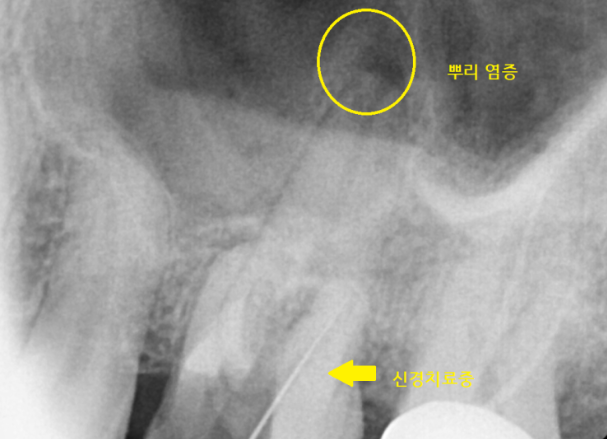

231222

치아 뿌리 염증은 신경치료를 통해

농을 배출했습니다.

240115

신경치료 후 보철을 제작

문제가 있는 치아를 어떻게든 살려

좀 더 쓸 수 있게 치료를 마무리해드렸습니다.

치료할 수 있을데까지 치료합니다.